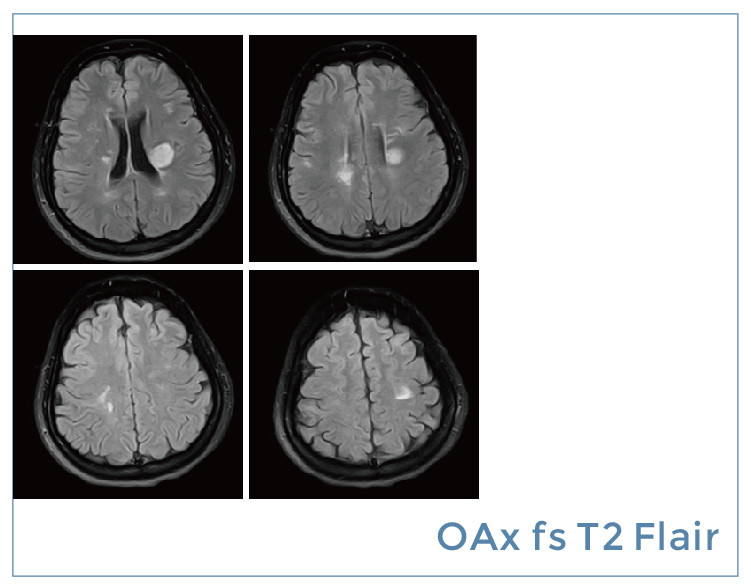

【朗润影像档案】磁共振影像病例分享(编号20190823)